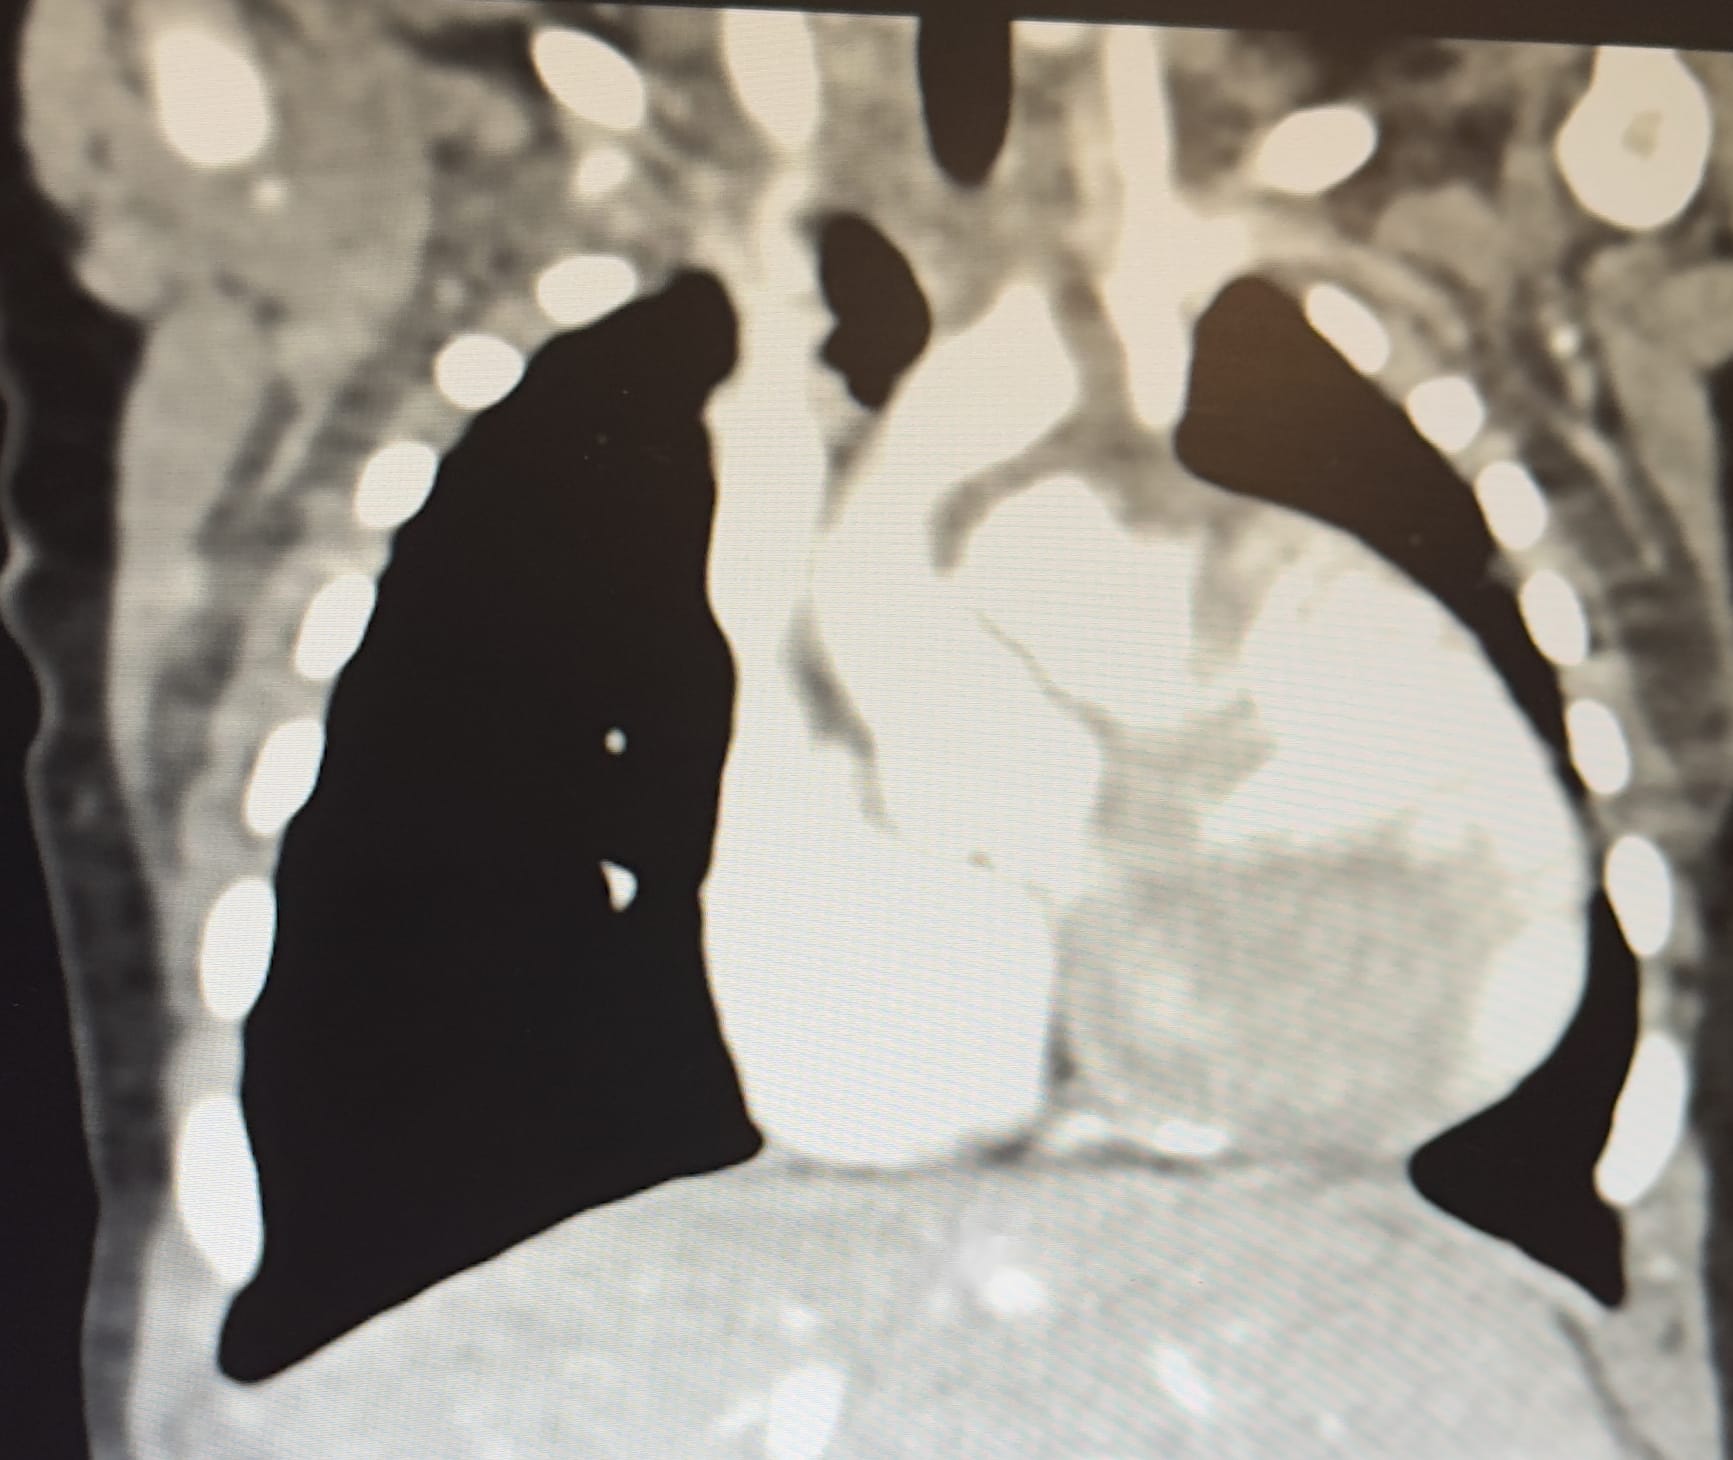

Update she will be in Surgery at 2:00PM, they will be doing the repair to connect the RPA & the LPA together with a shunt, they also said they might go ahead and do the repair for the Tetralogy of Fallot as well, they said it just depends on how the first repair goes so they are playing it by ear at the moment.

Here is a Live we did Saturday, this gives an update as well as the procedure they will be performing, it is open heart surgery but only doing repair to the Discontinuous Pulmonary Branch Atresia, then will have another open heart surgery around 6 months old. Illyana's Heart

Illyana has went back a little she is fighting hard her heart is extremely sick, she is back on the vapotherm she was doing well but her heart is making it very hard to breath, ENT are going to run a scope to her air ways Monday and make sure what they are seeing is accurate, we seen a live CT Scan and we are potentially looking at Big Surgery next week, she has also been diagnosed with DiGeorge syndrome (chromosome 22 deletion "we normally have two copies of chromosome 22 in each cell") she is missing part of the 22 chromosome.

Big Brother, Big Sister, Cousin Autumn, Nana, and Papa came to see Illyana tonight. Isiah was the sweetest and held my hand the whole walk from my room to the NICU to see baby sister. These babies are in love with baby sister and they are ready for her journey of healing to be done so they can teach her all the fun things big kids get to do. It made my Mama heart happy to see them all together and how they interacted with her they did amazing which I knew they would. Helping Mommy Helping Mommy Praying over Illyana Loving on Baby Sister Proud Big Brother Proud Big Sister We spoke with the Cardiologist this evening, So originally we found out she had TOF/APV that stayed the same but now Discontinuous Pulmonary Branch Atresia was added, which 1 in every 200,000 to 1 in every 300,000 are born with just this one heart disease has been added to the diagnosis, this has increased how rare the condition is from the 0.2% to 0.4% to now a 1000 times rarer than original diagnosis, also has been confirmed Illyana only has 1 kidney.